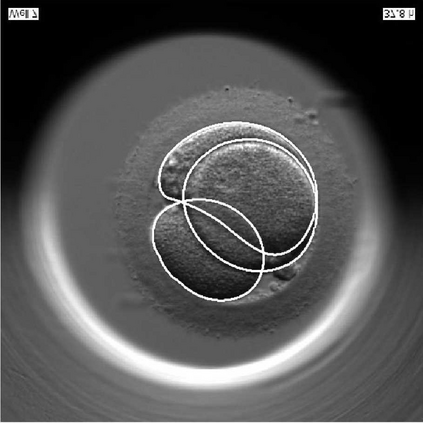

We present a novel method for identification of the boundary of embryonic cells (blastomeres) in Hoffman Modulation Contrast (HMC) microscopic images that are taken between day one to day three. Identification of boundaries of blastomeres is a challenging task, especially in the cases containing four or more cells. This is because these cells are bundled up tightly inside an embryo's membrane and any 2D image projection of such 3D embryo includes cell overlaps, occlusions, and projection ambiguities. Moreover, human embryos include fragmentation, which does not conform to any specific patterns or shape. Here we developed a model-based iterative approach, in which blastomeres are modeled as ellipses that conform to the local image features, such as edges and normals. In an iterative process, each image feature contributes only to one candidate and is removed upon being associated to a model candidate. We have tested the proposed algorithm on an image dataset comprising of 468 human embryos obtained from different sources. An overall Precision, Sensitivity and Overall Quality (OQ) of 92%, 88% and 83% are achieved.